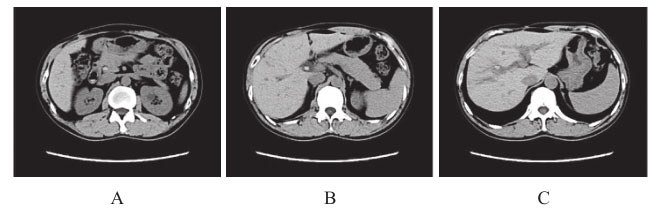

6.上腹部CT及MRCP 肝右叶胆管结石伴远端胆管扩张,胆总管上段及下段结石(图1、图2)。

图1 MRCP:肝右叶胆管结石,胆总管结石

图2 上腹部CT:肝右叶胆管结石及胆总管结石